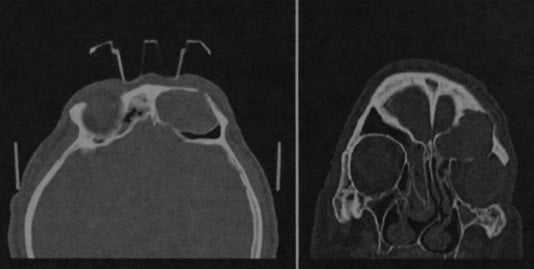

Пациент с часто появляющейся под кожей медиального угла левого глаза флуктуирующей припухлостью.

КТ в горизонтальной (а) и вертикальной (b) проекциях. Расширенный слезный мешок в области медиального угла глаза (1). Слезный проток также расширен на всем протяжении (2), заканчивается в нижнем носовом ходе и, по-видимому, закупорен.